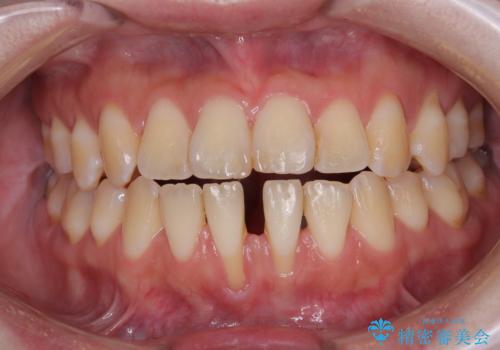

矯正の後戻りによるすきっ歯と歯肉退縮 根面被覆と部分矯正

- 学生時代の矯正治療の後戻りと、それに伴う下顎前歯西肉退縮を気にして来院された患者様です。

舌の突出癖が著しく、それが原因で後戻りと歯肉退縮を起こしている状態でした。

舌のトレーニングをしっかりと行っていくことを前提に、歯肉移植による根面被覆と、部分矯正によるすきっ歯の改善を行うこととしました。

歯肉移植と矯正治療後には非常に満足のいく仕上がりとなりましたが、舌の突出癖は残存しており、今後歯肉退縮とすきっ歯になるリスクを抱えた状態での治療終了となりました。